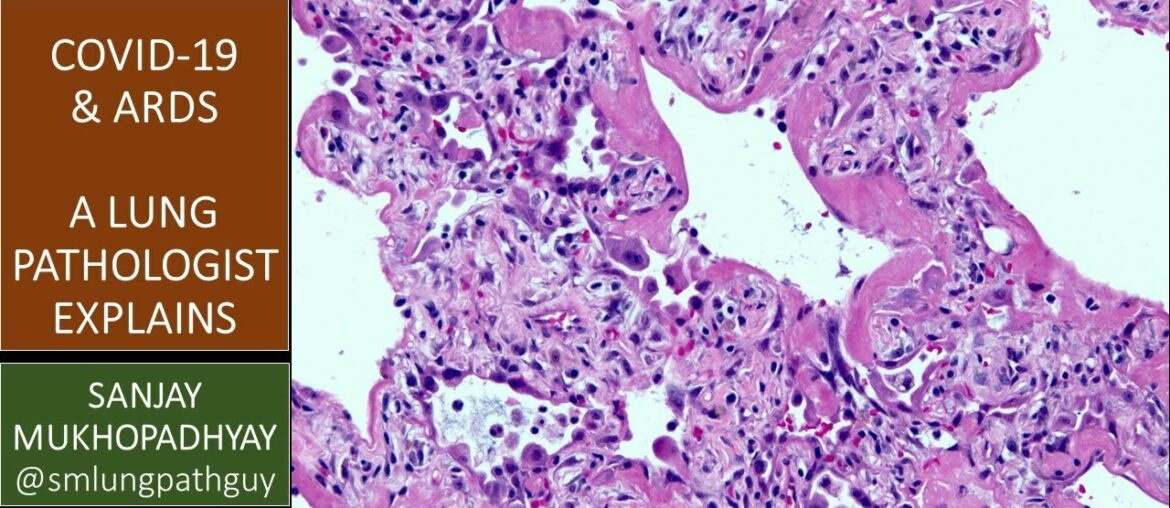

COVID-19 can kill: a lung pathologist explains what ARDS means and why it's important

COVID-19 COVID-19 can kill: a lung pathologist explains what ARDS means and why it's important March 17, 2020